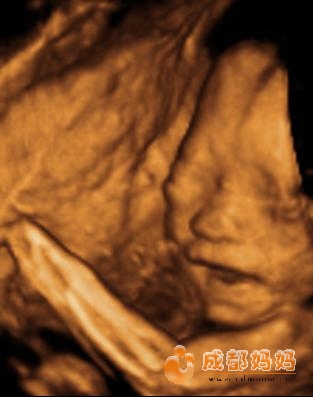

怀孕一个月胎儿彩超图片如下:

怀孕一个月胎儿彩超图片